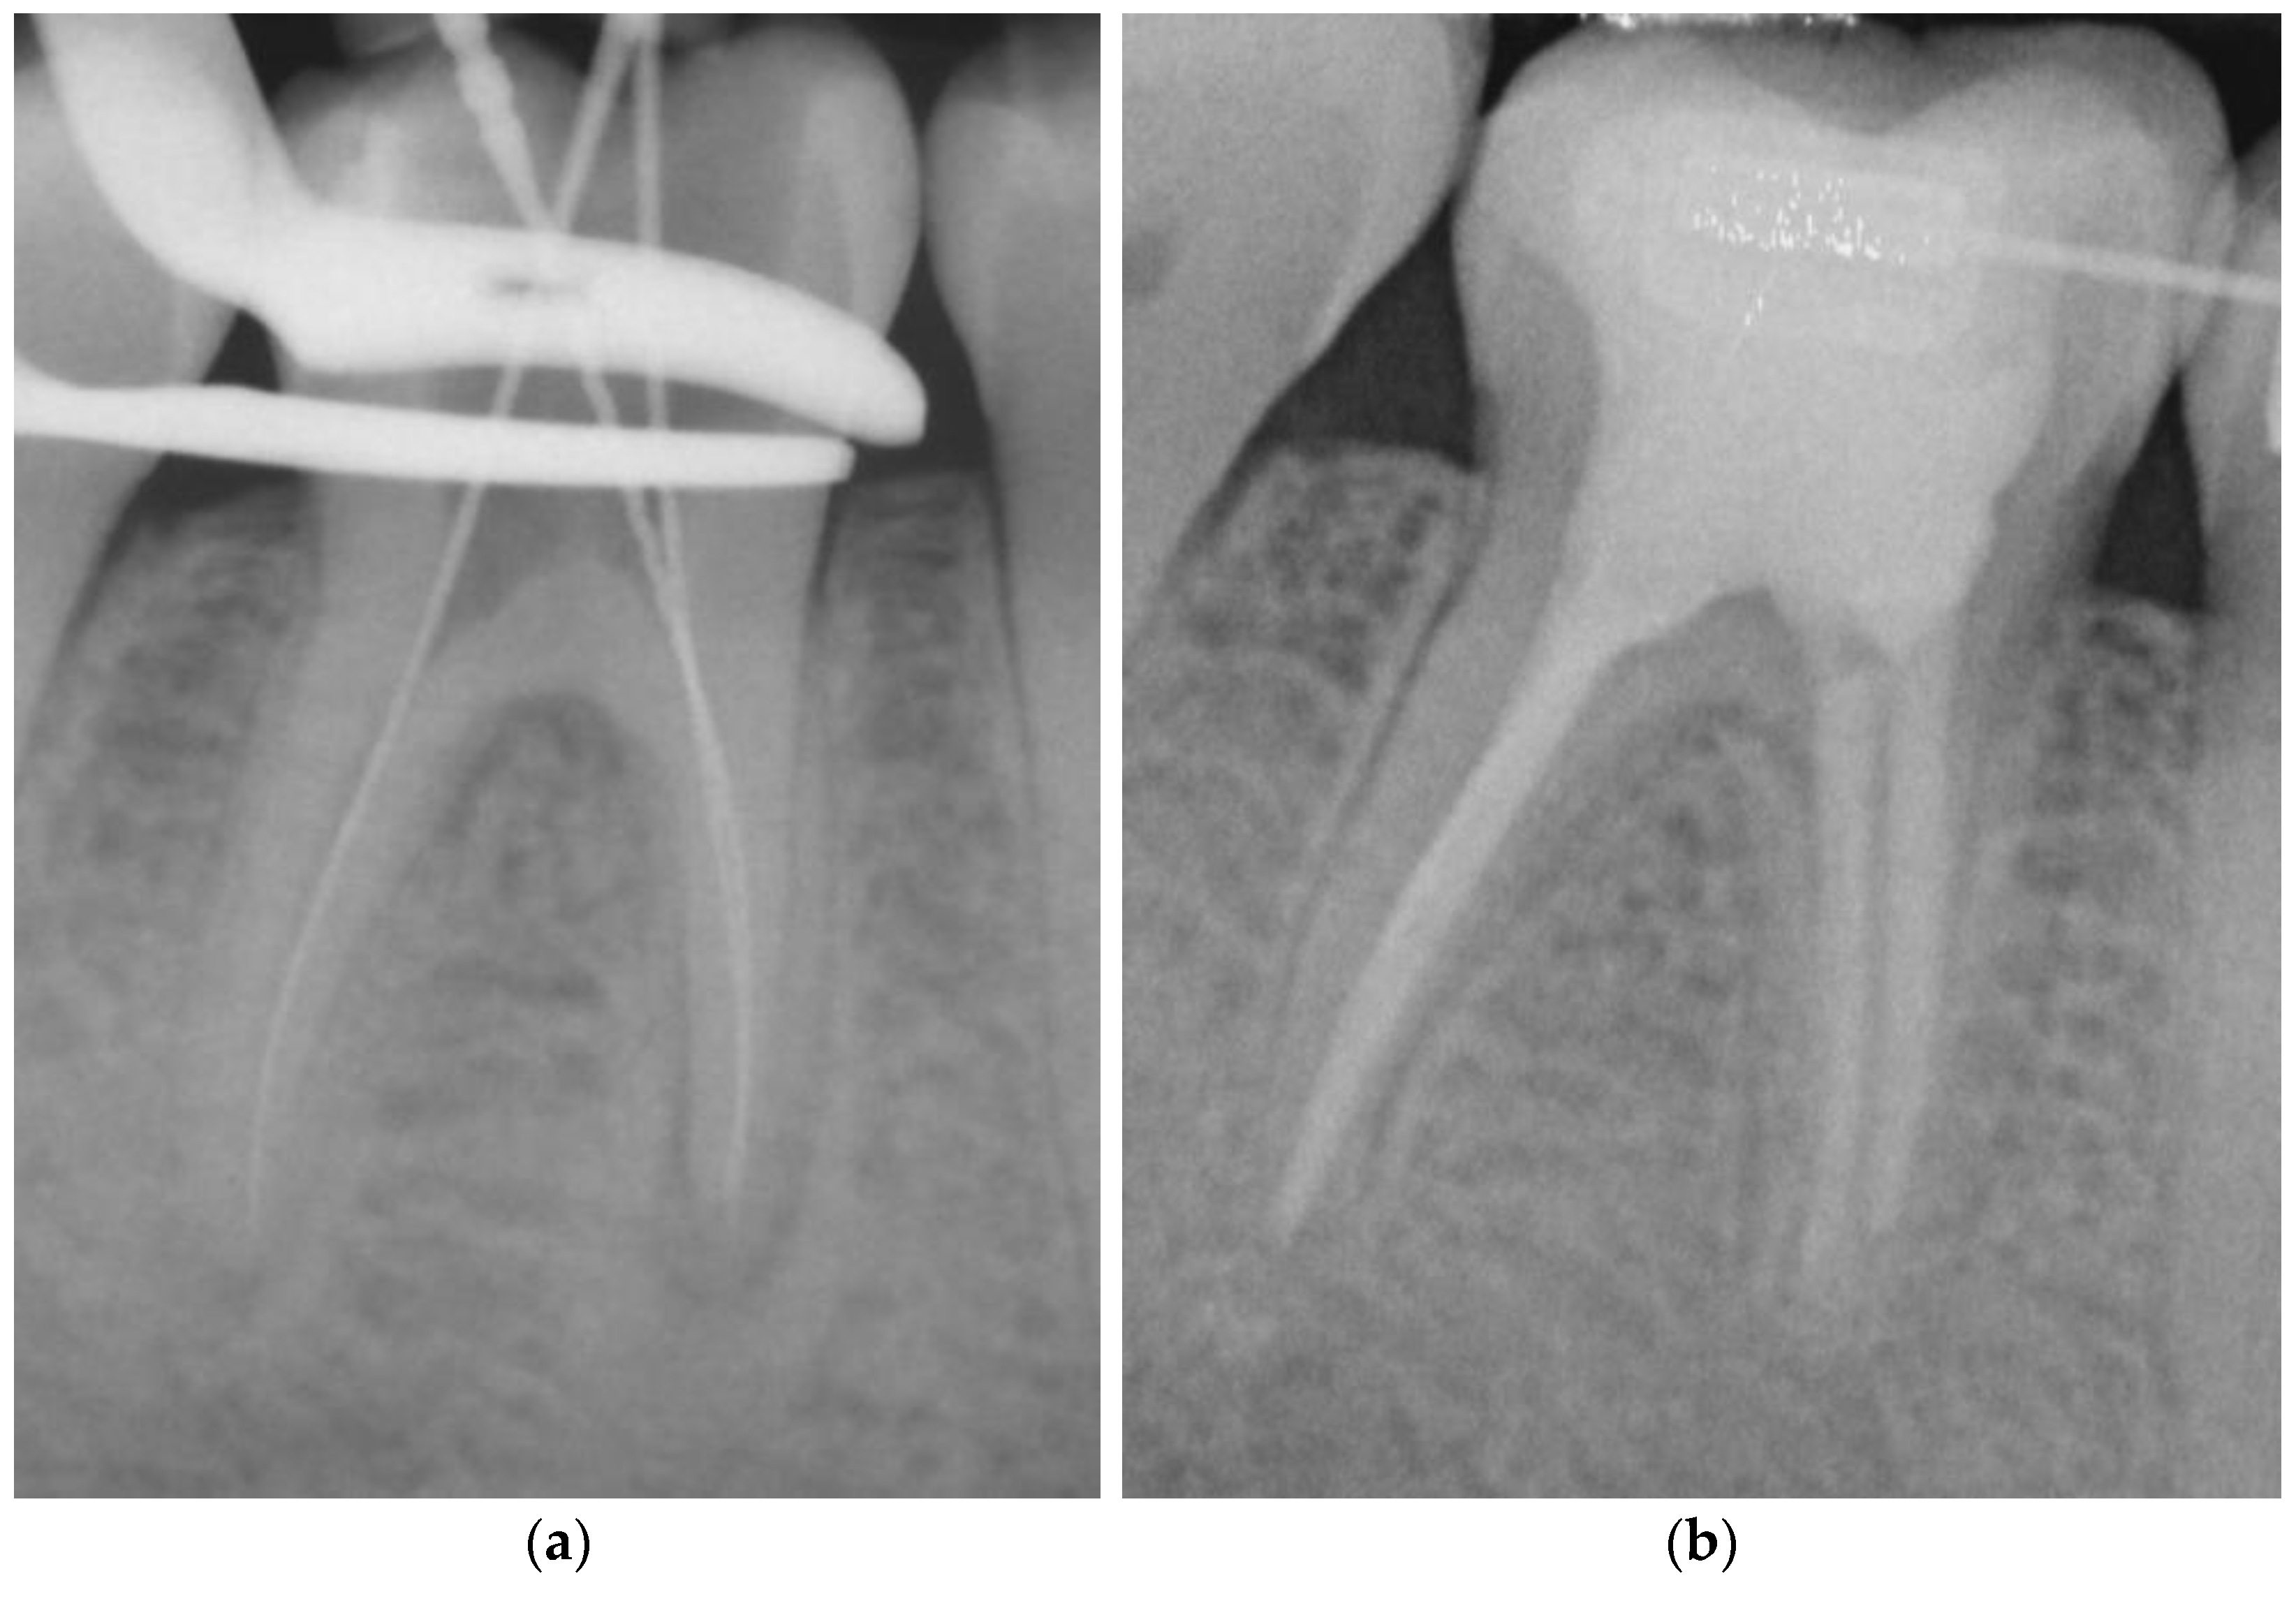

Figure 1. Representative example of root canal filling with Resilon® using the continuous wave of condensation technique (CWR); working length radiograph of tooth 36 (a); 6-year follow-up radiograph showing complete apical healing (b). - Matching-taper single-cone obturation with gutta-percha and the epoxy-resin-based sealer AH Plus® (SCGP) (Figure 2).

Figure 2. Representative example of root canal filling using the single-cone obturation technique with gutta-percha and AH Plus® (SCGP); working length radiograph of tooth 26 (a); 7-year follow-up radiograph showing complete apical healing (b). - Matching-taper single-cone obturation with gutta-percha and the silicon-based sealer GuttaFlow® (SCGF) (Figure 3).